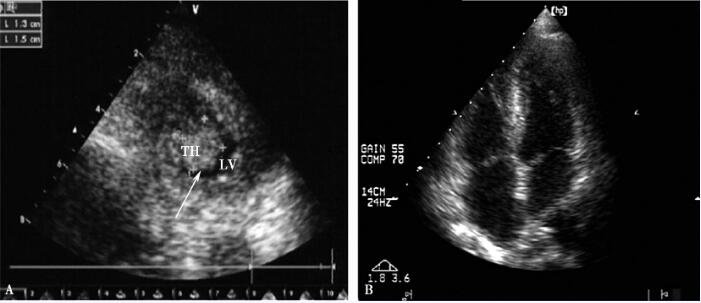

住院第16日进食后突然出现上腹部疼痛,呈钝痛,无肩背部放射痛,无恶心、呕吐、腹泻、呕血及黑便。查体:左上腹压痛、反跳痛,无肌紧张。急诊超声及CT示脾梗死、胆囊炎、腹膜后多发淋巴结肿大、左心室近心尖部血栓(图2、图3)。明确诊断为左心室血栓、急性左心功能不全、阵发性房扑、急性脾梗死。给予低分子肝素4250IU皮下注射每12小时1次,华法林2.5mg每天1次抗凝治疗3天后,INR由1.46升至2.81,停用低分子肝素。同时按需口服双氯芬酸钠止痛,继续利尿纠正心衰,抗结核、减弱抗感染力度(换为头孢他啶)治疗。

图2 上腹部增强CT

左心室血栓、脾梗死(箭头所示)

图3 心脏超声

A.左心室血栓(箭头所示);B.左心室血栓消失

住院第28日复查心脏彩超示左心室血栓消失(图3),第29日CT引导下经皮肺穿刺活检病理结果回报:小灶型干酪样坏死组织,周围包裹上皮样细胞、多核巨细胞,伴间质、纤维组织增生,慢性炎性细胞浸润。抗酸染色找到抗酸杆菌(见图4)。

A.干酪样坏死(箭头所示);B.抗酸杆菌(箭头所示)